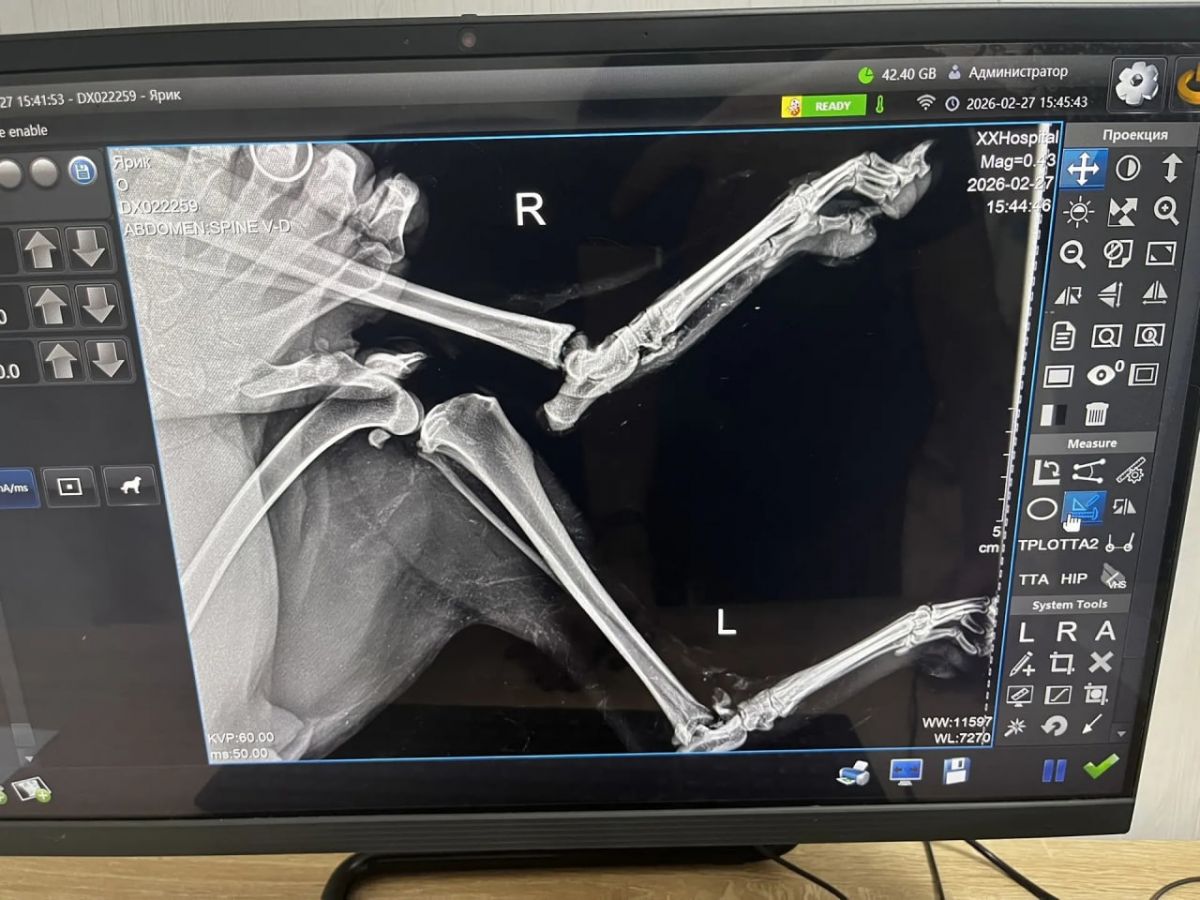

Как сообщает администрация приюта «Майский день», к сожалению, у собаки были выявлены серьезные травмы: скальпированная рана хвоста и переломы скакательных суставов обеих задних конечностей. Для восстановления ей потребуется сложная и дорогостоящая операция, а также дальнейшая реабилитация.